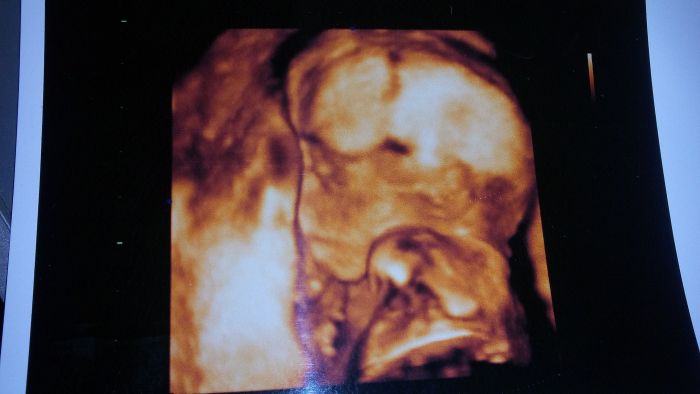

Ahoj holky tak jsme po utz a už to máme na 150% holčičku, měla vaječníky nebo co to :D Ale fotit se nechce Terezka naše, měla hlavu furt v placentě a ne a ne se ukázat má 300g a jsem 19+5 a dle MS 20+1tt ale říkal že tonje normalka fotky nic moc no jak rikam nechtěla se ukázat za celé tehu jsem pribrala 2,1 kg a teď za ty 3 týdny 1,3 kg :D tlak normalka nizsi, přítel no chudak asi ani nevěděl na co se kouká a 3D říkal že je nechutné :D atbmunukazuju jen černobílé :D jinak na další kontrolu 24.11. A na cukr nvm? To asi až pak nebo vůbec?

Taky velka gratulace k Terezce :-) Ja ani nevim jestli nam 3D pujde. Ale vypada to všelijak. No až bude na světě, tak to bude princezna :-)